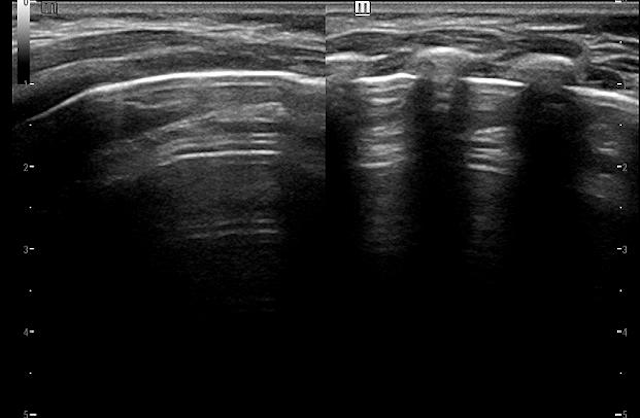

正常肺超声图

超声医学科主任黄永介绍,在儿科领域,肺部超声相较于成人检查更具独特优势。新生儿的胸廓呈桶状,肋骨水平走向,肋间间隙较宽;儿童的肋骨钙化不完全,肺组织含气量较少,肺间质相对丰富。这些优势使得肺组织更易被超声波穿透,从而获得较为清晰的超声图像。